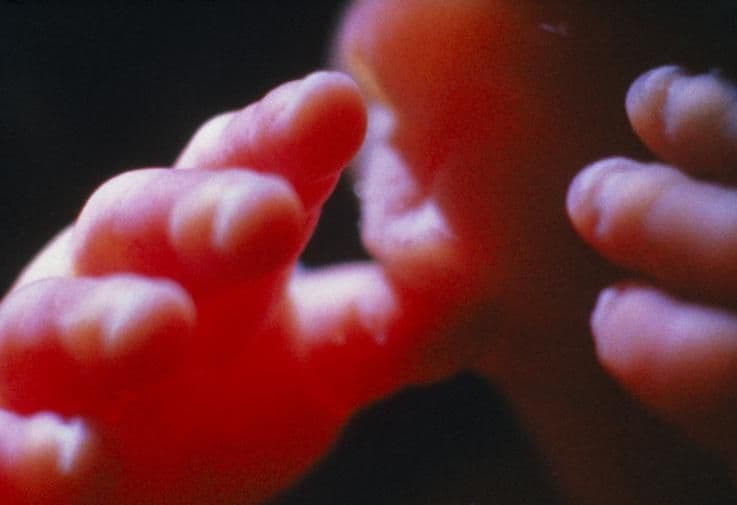

This close-up of the fingertips shows that the nail beds have formed and the nails are starting to grow. The nails have not yet hardened: this prevents your baby from scratching himself accidentally while he has no control over hand movements.